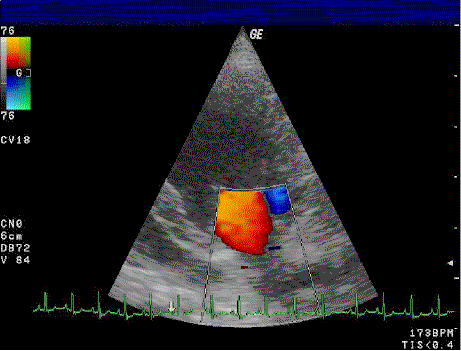

فحص الإيكو على القلب (Echocardiography)

يُعد فحص الإيكو على القلب من أهم وأشهر فحوصات القلب غير التداخلية، ويعتمد على الموجات فوق الصوتية لإظهار صورة حية لعضلة القلب والصمامات وتدفق الدم.

ويُستخدم فحص الإيكو للكبار والأطفال في العديد من الحالات، أبرزها:

- تقييم كفاءة عضلة القلب وقوة ضخ الدم

- تشخيص أمراض صمامات القلب

- اكتشاف العيوب الخلقية بالقلب لدى الأطفال

- متابعة حالات ضعف عضلة القلب

- تقييم تأثير ارتفاع ضغط الدم على القلب

يوفّر مركزنا فحص الإيكو للأطفال والكبار باستخدام أحدث أجهزة الموجات فوق الصوتية، مع مستوى عالٍ من الدقة التشخيصية وتحت إشراف نخبة من أطباء الأشعة والقلب.